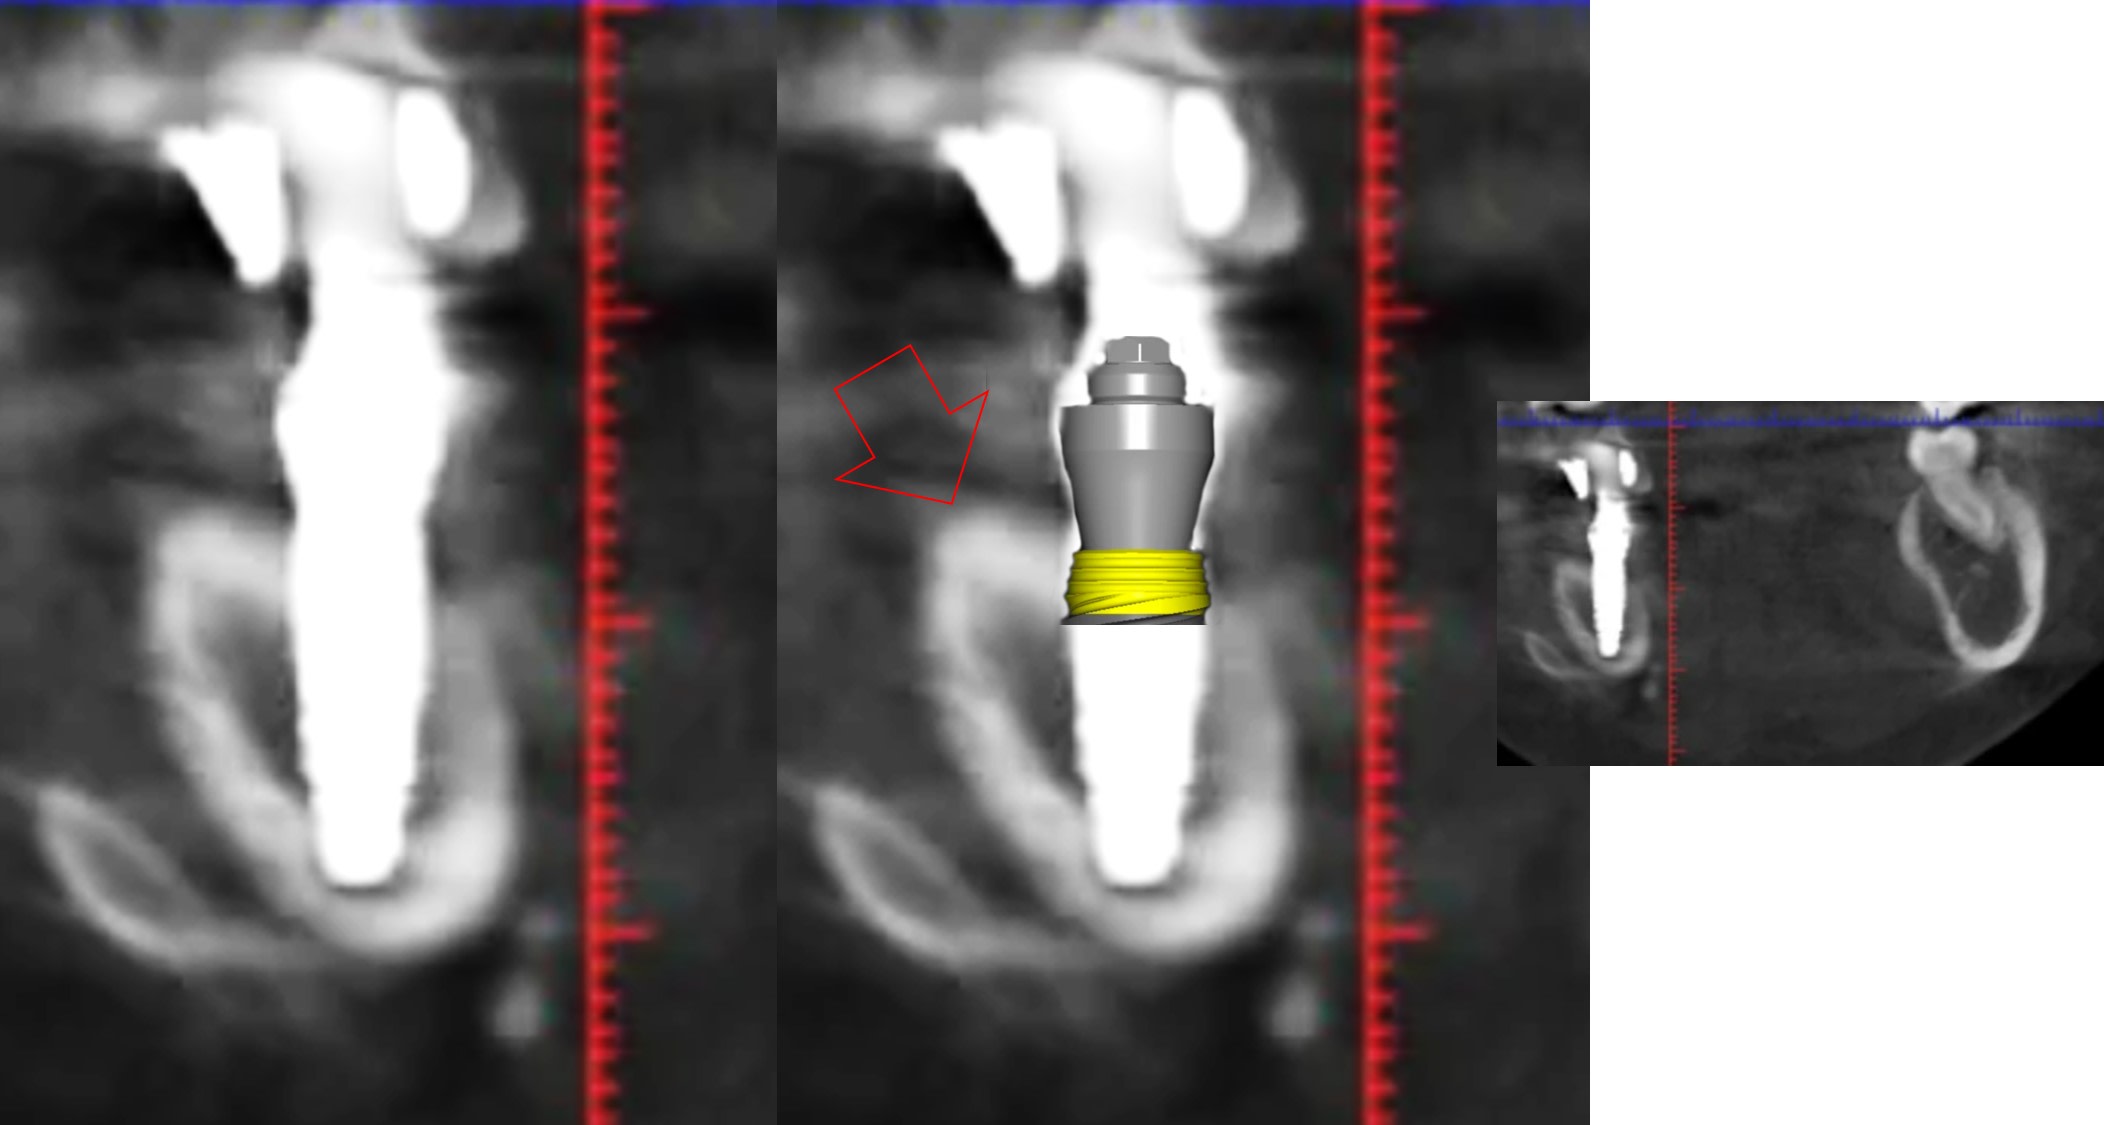

ce qui devrait etre acté c'est que cet implant devrait etre dans l'os... ce qui est tres loin d'etre le cas.

mais bon a part l'implant pas dans l'os : 10/10 :)

tu devrais faire des triangles pour faire croire qu'il est convenablement enfoui...

Hokusaï tu ne vois pas avec les dessins de Posit ? les implants sont parfaitement posés

Regarde bien. On ne voit que ça.

Tu sais Posit il n’y a pas mort d’homme à reconnaître les choses. Je pense que ton système de guide est un bon système.

Perso ça m’est arrivé de faire bien pire. Genre des implants qui ne prennent pas. J’ai même récupéré un implant que j’avais balancé dans la cavité nasale, idem dans le sinus. Ça m’est arrivé de poser quelques couronnes sur des implants non osteo intégrés (alors que j’étais persuadé qu’ils étaient osteo intégrés). À mes tous débuts ça m’est déjà arrivé une fois ou deux de faire des trous ovalaires, je pose l’implant , ah merde l’implant flotte par ma faute. Ça m’est arrivé de faire des expansions où des implants n’étaient pas dans l’axe idéal. Je reconnais mes erreurs, je repose gratuitement . Rien de grave

Toi ton truc : c’est rien du tout ! Hokusai te cherche parce que tu l’as critiqué avant sur son travail. Mais dans le fond le patient n’avait plus de mandibule, et là grâce aux chirurgiens et ton travail, le voilà avec des dents …. Franchement il n’y a rien de très très grave . Ça ne coûte rien de reconnaître les choses. :)

> ce qui aurait ete opportun c est d enfuir convenablement ces implants;)

> l implant qui a 5 spires du col a l air a la pose c est ok pour toi ???

> dire que tu presentes ca comme le summum :)))

> vous avez pris des radio per op et vous avez laisse comme ca ?

:))) on reparle de ton implant extra osseux la ???

heureusement que c est ton plus beau cas ;)

Où tu vois 5 spires extra osseuses ?

sur tes radios... apres je pensais en effet que le col de cet implant etait micro fileté... mea culpa... ;)

dans tous les cas l implant c est dans l os ;)

Tu peux être préoccupé par ça où t'intéresser au sujet par exemple une pano nous donne t elle une indication fiable sur la position d'un implant ?